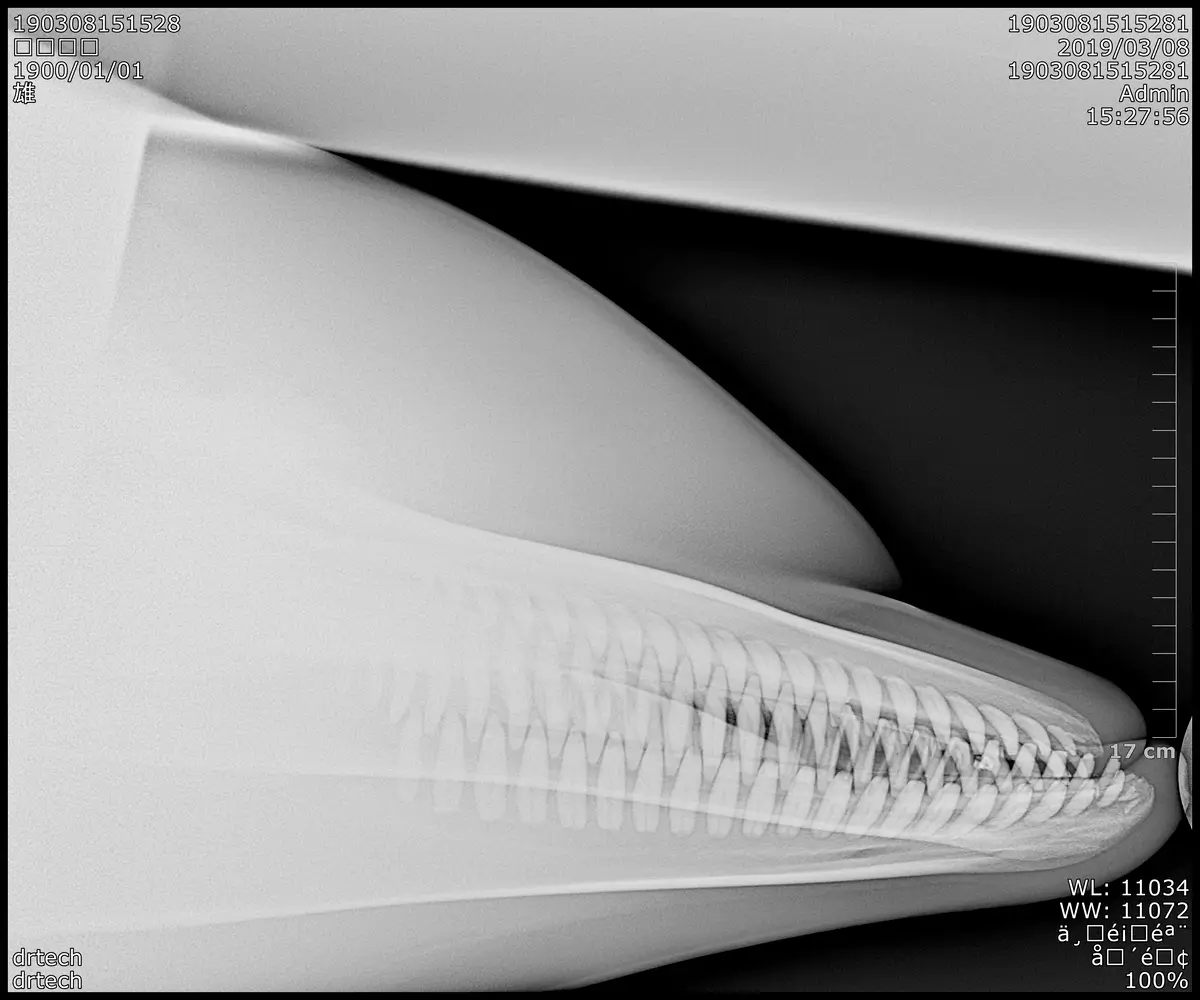

• ペンギン、バク、ヒグマなど、多種多様な動物園・水族館動物の診療実績あり

• 園館・エキゾ・鳥類専門医との共同研究、関連動物病院への就職実績多数